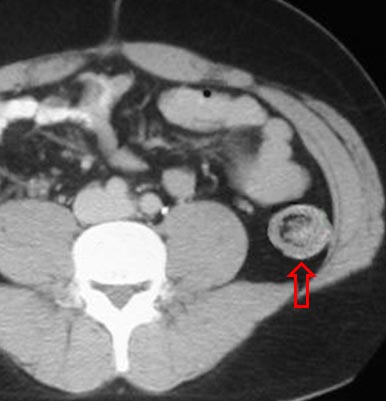

SIGNO DE LA SEMILUNA EN DONUTS

La invaginación intestinal provoca una imagen de donut o diana visible tanto por ecografía como por TC. La presencia de grasa mesentérica acompañando al asa invaginada, se ve como una semiluna (hiperecogénica en ecografía, hipodensa en TC) dentro de la imagen del donut.

Corte axial de TC de abdomen de otro paciente que muestra una semiluna con la densidad grasa del mesenterio en una invaginación ileo-ileal.

La referencia bibliográfica es un artículo de G del Pozo, J C Albillos y D Tejedor en Radiology: Intussusception: Us finfings with pathologic correlation. The crescent-in-doughnut sign. El abstract puede consultarse en: http://pubs.rsna.org/doi/abs/10.1148/radiology.199.3.8637988.